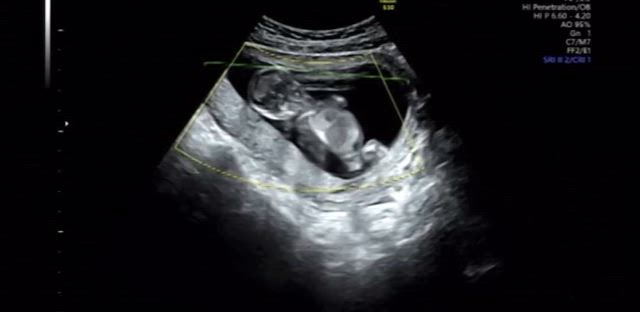

【12w6d】エコーで見えた我が子の癖(動画有)